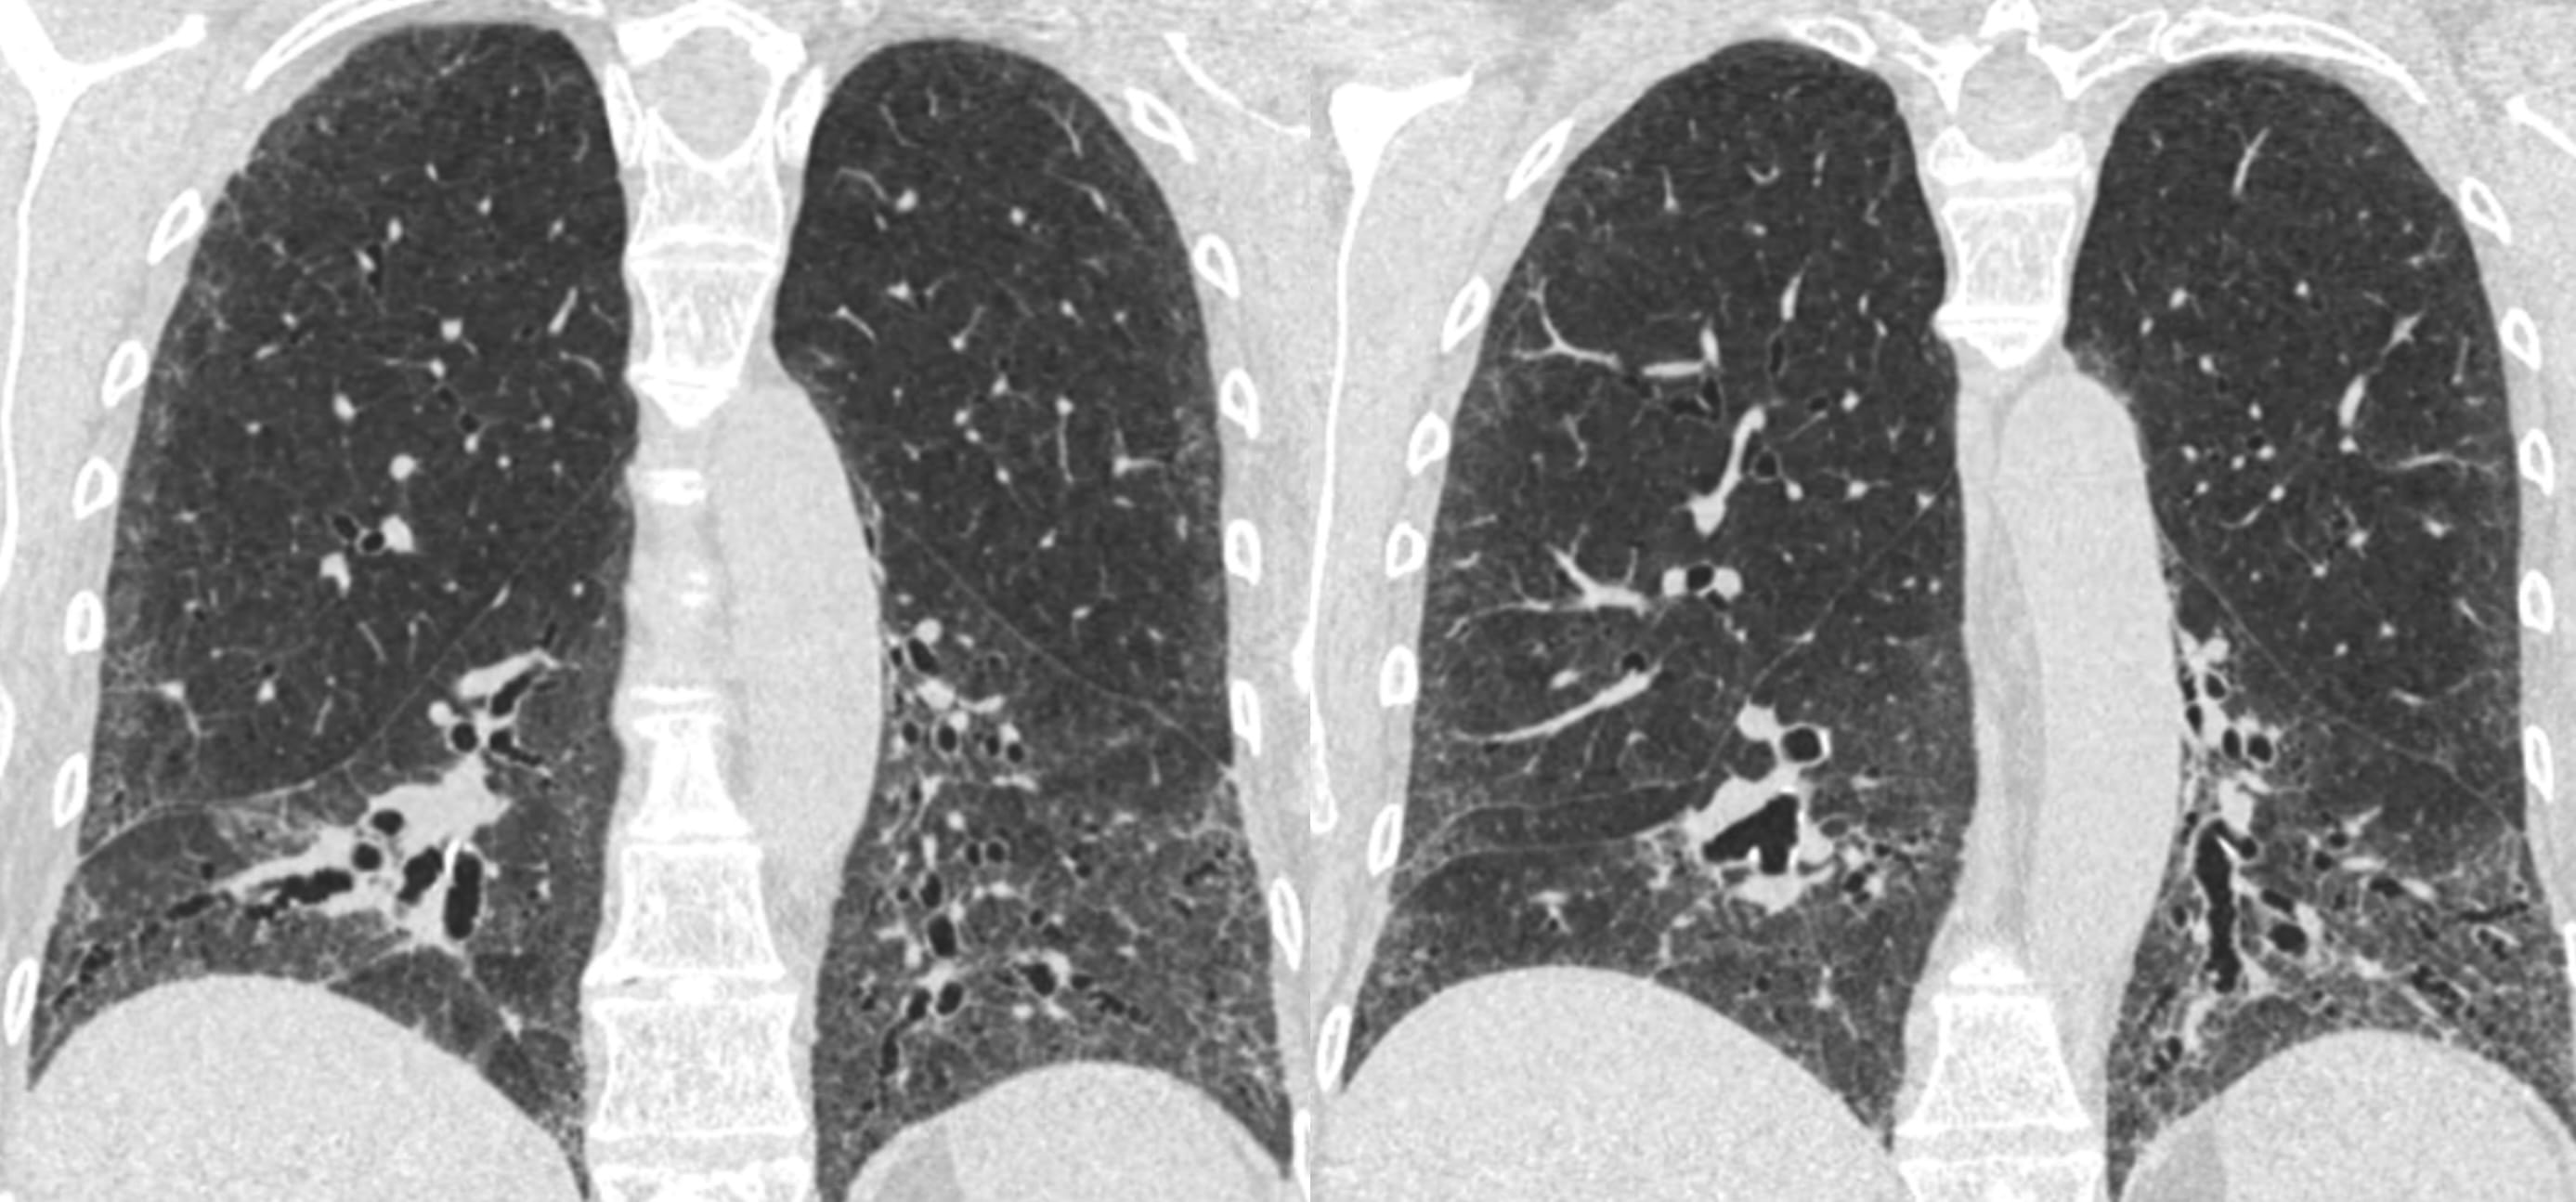

- Progressive Pulmonary Fibrosis